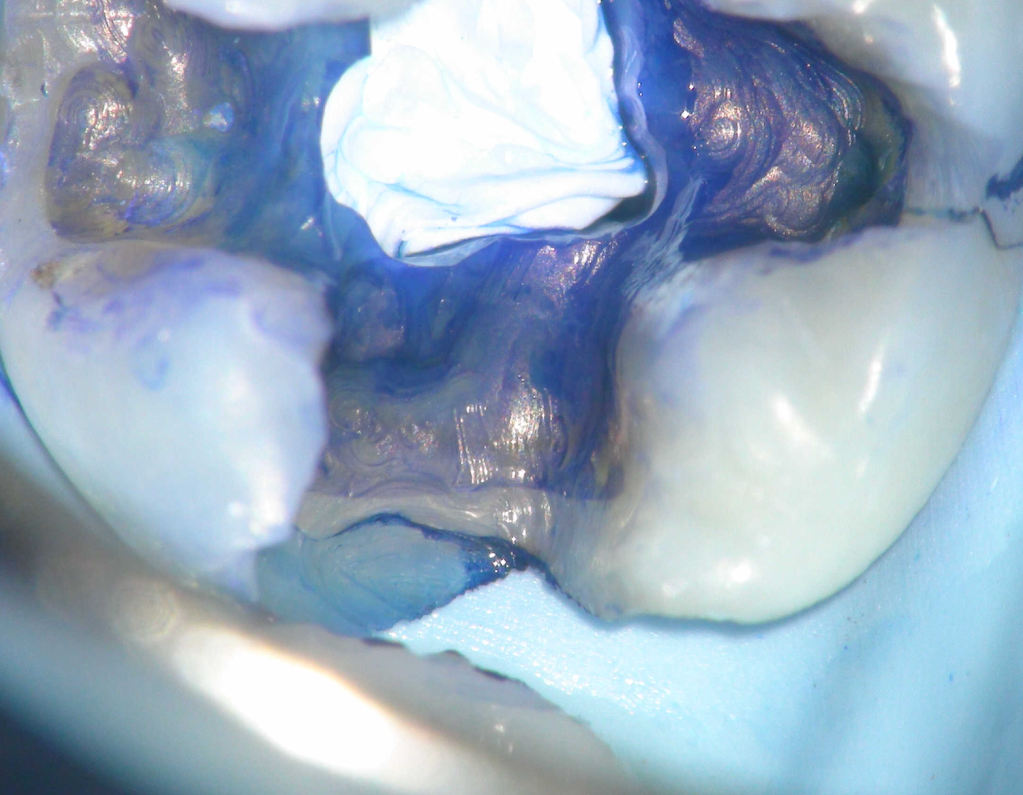

Pulpotomía biodentine + reco preendio